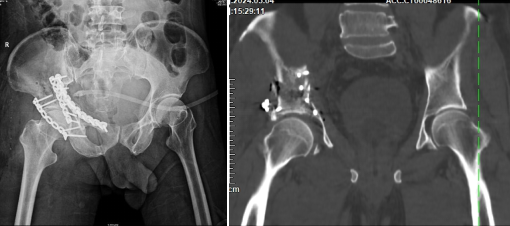

術(shù)前DR、CT重建片

為了攻克這一難題,云城區(qū)人民醫(yī)院骨科團(tuán)隊(duì)與華南理工大學(xué)解剖教研室、廣州市第一人民醫(yī)院數(shù)字骨科專家丁煥文采用MDT模式會診,采用3D打印技術(shù)輔助手術(shù)。數(shù)字化醫(yī)療公司通過CT數(shù)據(jù)合成3D圖像,精確復(fù)原了患者所有碎骨塊的大小和位置。云城區(qū)人民醫(yī)院骨科團(tuán)隊(duì)在體外模擬了手術(shù)復(fù)位固定過程,作出精準(zhǔn)術(shù)前規(guī)劃,為手術(shù)的成功奠定了堅(jiān)實(shí)基礎(chǔ)。